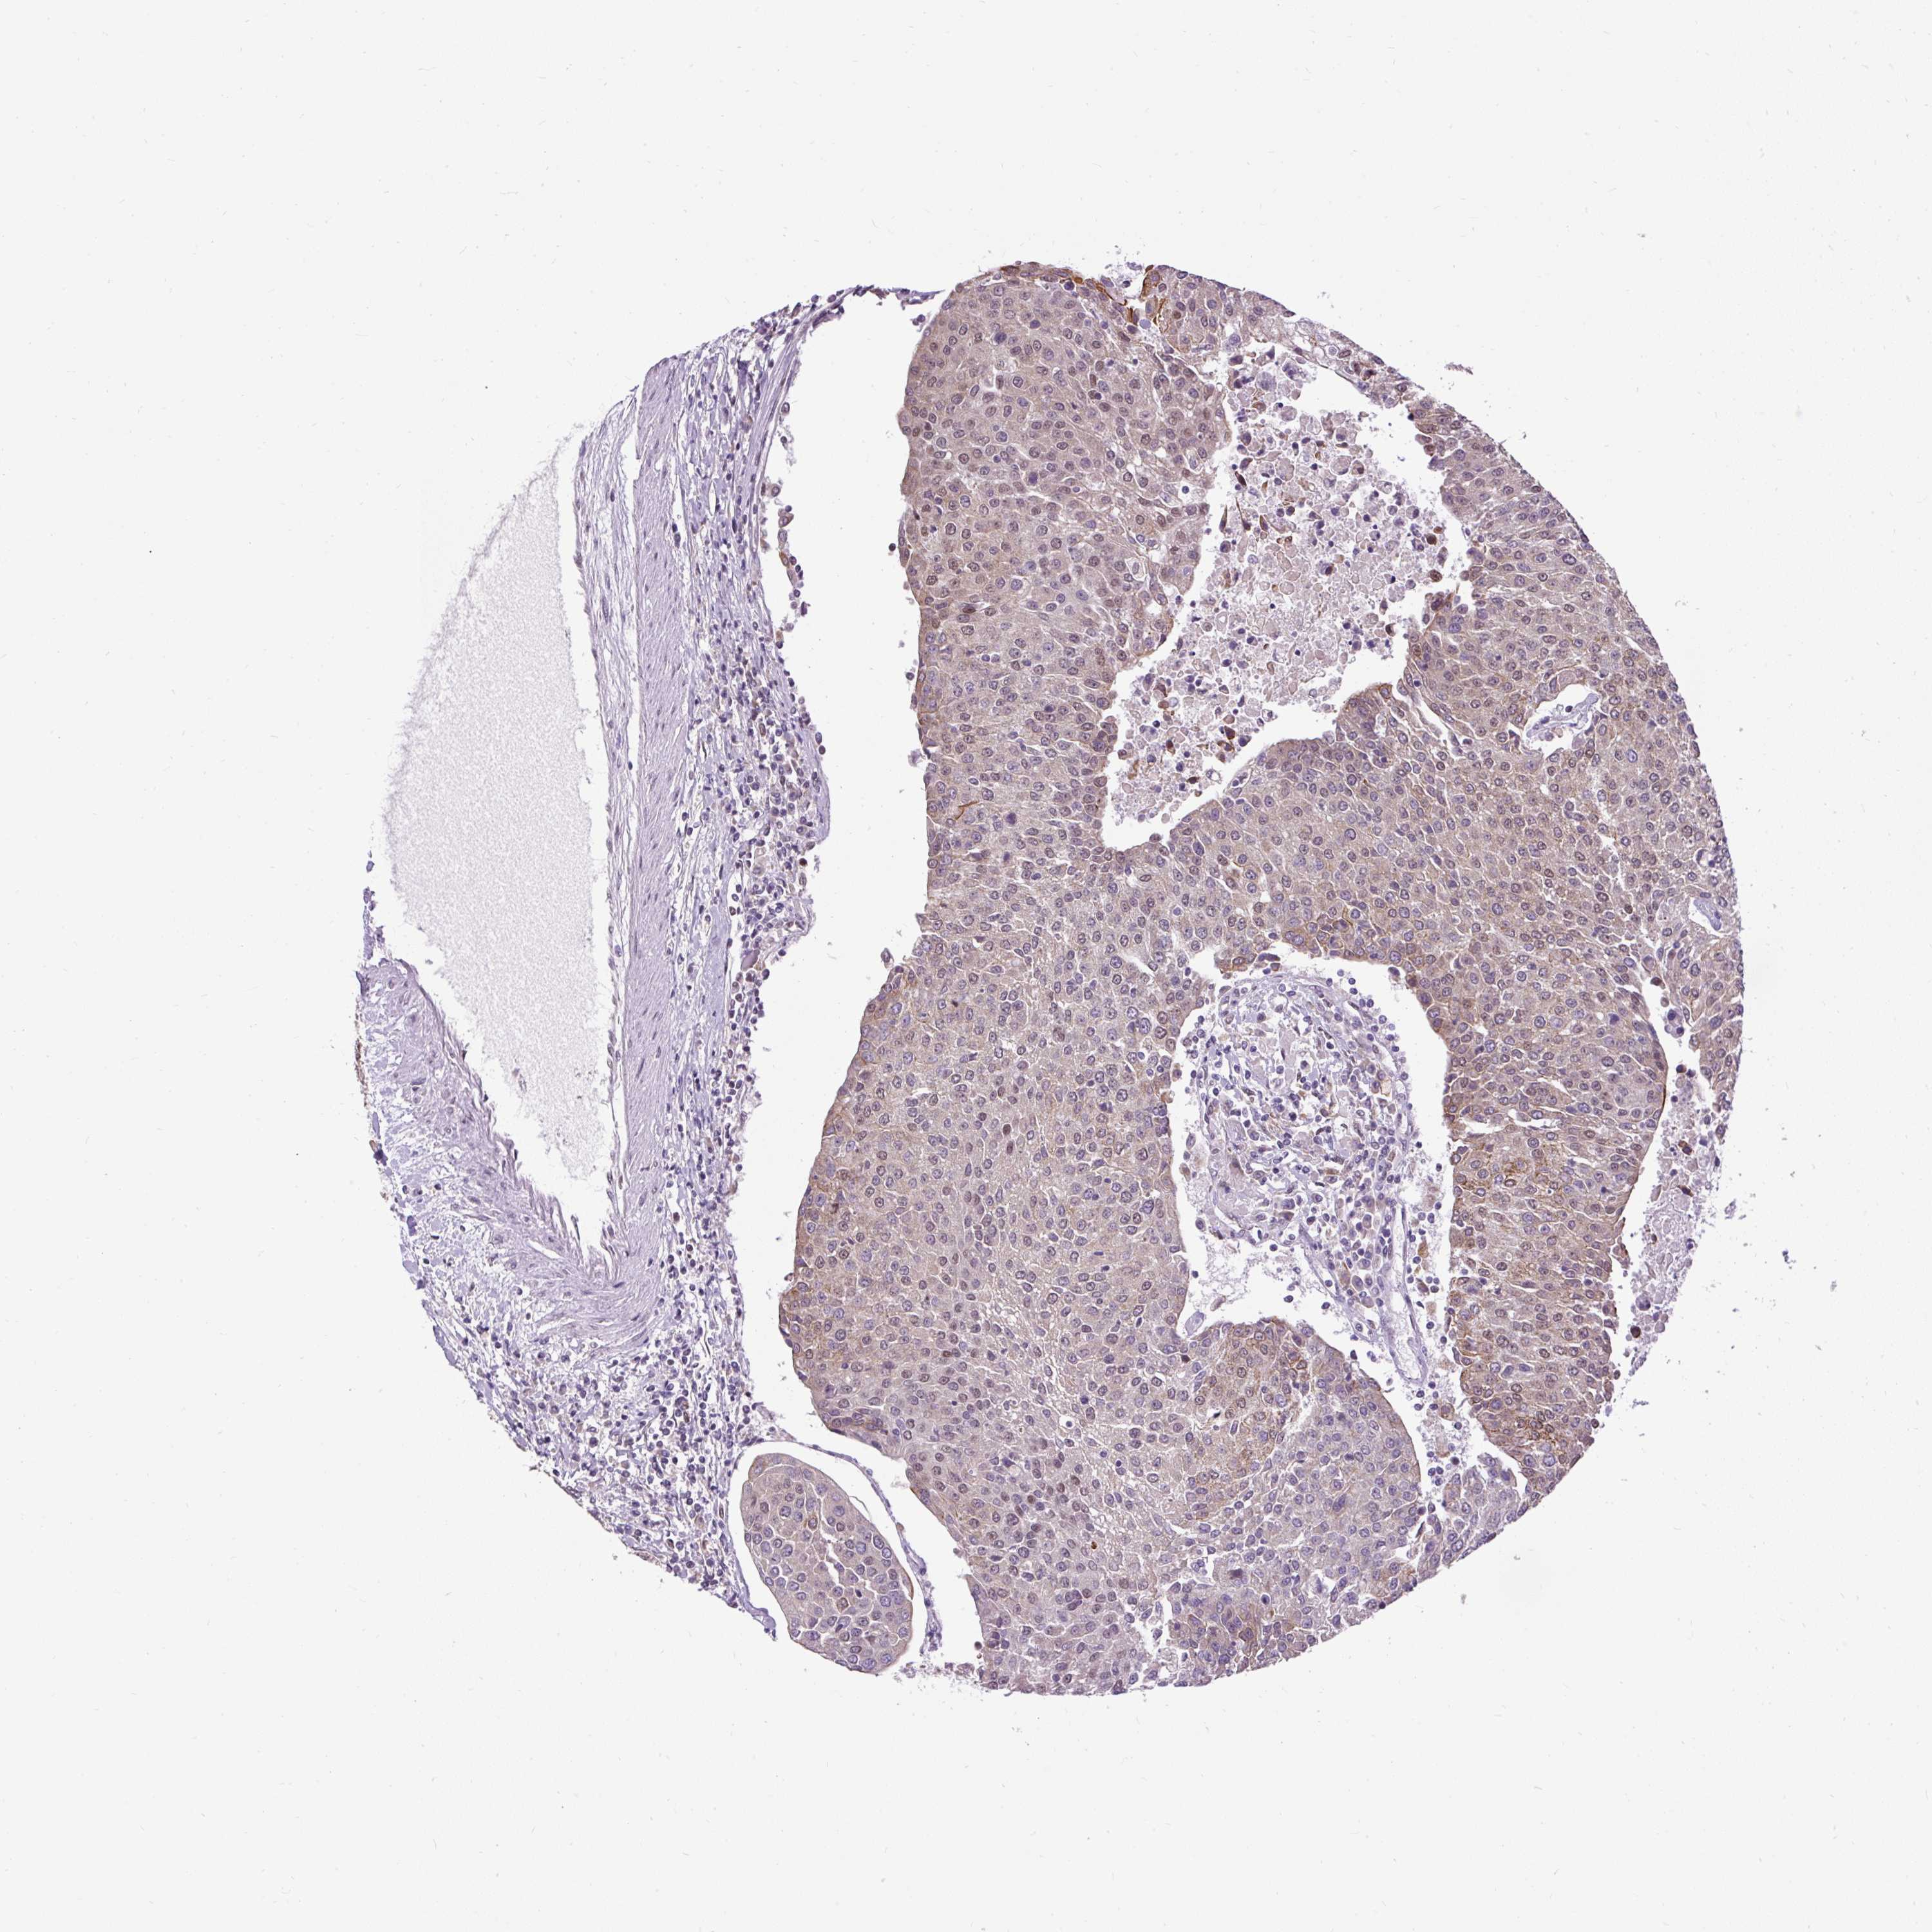

UROTHELIAL CANCER - Protein expressioni

A mouse-over function shows sample information and annotation data. Click on an image to view it in a full screen mode. Samples can be filtered based on level of antibody staining by selecting one or several of the following categories: high, medium, low and not detected. The assay and annotation is described here.

Note that samples used for immunohistochemistry by the Human Protein Atlas do not correspond to samples in the TCGA dataset.

Antibody stainingi

Antibody staining in the annotated cell types in the current human tissue is reported as not detected, low, medium, or high, based on conventional immunohistochemistry profiling in selected tissues. This score is based on the combination of the staining intensity and fraction of stained cells.

Each image is clickable and will lead to virtual microscopy that enables deeper exploration of all samples and also displays staining intensity scores, fraction scores and subcellular localization as well as patient and tissue information for each sample.

Antibody HPA055779

Staining

High

Medium

Low

Not detected

Intensity

Strong

Moderate

Weak

Negative

Quantity

>75%

75%-25%

<25%

None

Location

Urothelial carcinoma, High grade

Urothelial carcinoma, NOS

Urothelial carcinoma, Low grade